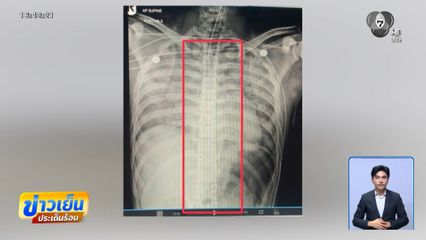

ข่าวเย็นประเด็นร้อน - การเสียชีวิตของ "พลทหารเพรชรัตน์" ถูกระบุว่า เกิดจาก "หัวใจล้มเหลว" เรื่องนี้ยังไม่มีอะไรน่าติดใจเท่าปริศนา "ช้อนสั้น" ที่พบในเตาเผาศพ ซึ่งทางโรงพยาบาล ก็ให้ข้อมูลมาแบบอ้อม ๆ ว่า ผลเอ็กซเรย์ไม่พบว่ามีช้อนในร่างกายจริง ๆ ส่วนคำชี้แจงอื่น ๆ รอฟังกันได้เลย เย็นวันนี้

มีการชี้แจงจาก ผบ.เรือนจำมณฑลทหารบกที่ 12 ที่ส่งข้อมูลไปให้กับ นางสาวนิชนันท์ วังคะฮาต อดีตผู้สมัคร สส.ชลบุรี พรรคประชาชน และถูกนำไปโพสต์ลงโซเชียลฯ หนึ่งในข้อมูลที่มีการอธิบาย นอกเหนือจากภาพเอ็กซเรย์ ที่ต้องการยืนยันว่า ไม่มีช้อนในร่างกาย คือไทม์ไลน์ตั้งแต่ก่อนจนถึงตอนที่เข้ารับการรักษาและเสียชีวิต

สำหรับเรื่องความคาใจของญาติ ๆ จากการสอบถาม ผู้อำนวยการโรงพยาบาลค่ายฯ บอกว่า กองทัพบก จะเปิดเผยเรื่องนี้พร้อมกับญาติ ขณะที่มีรายงานข่าวว่า การรักษาที่เกิดขึ้นในวันนั้น แพทย์มีการสอดท่อช่วยหายในเข้าไปในร่างกาย และได้พาตัวไปเอ็กซเรย์ จึงเกิดภาพนี้ขึ้นมา ยืนยันว่า ไม่พบมีช้อนในร่างกายจริง ๆ